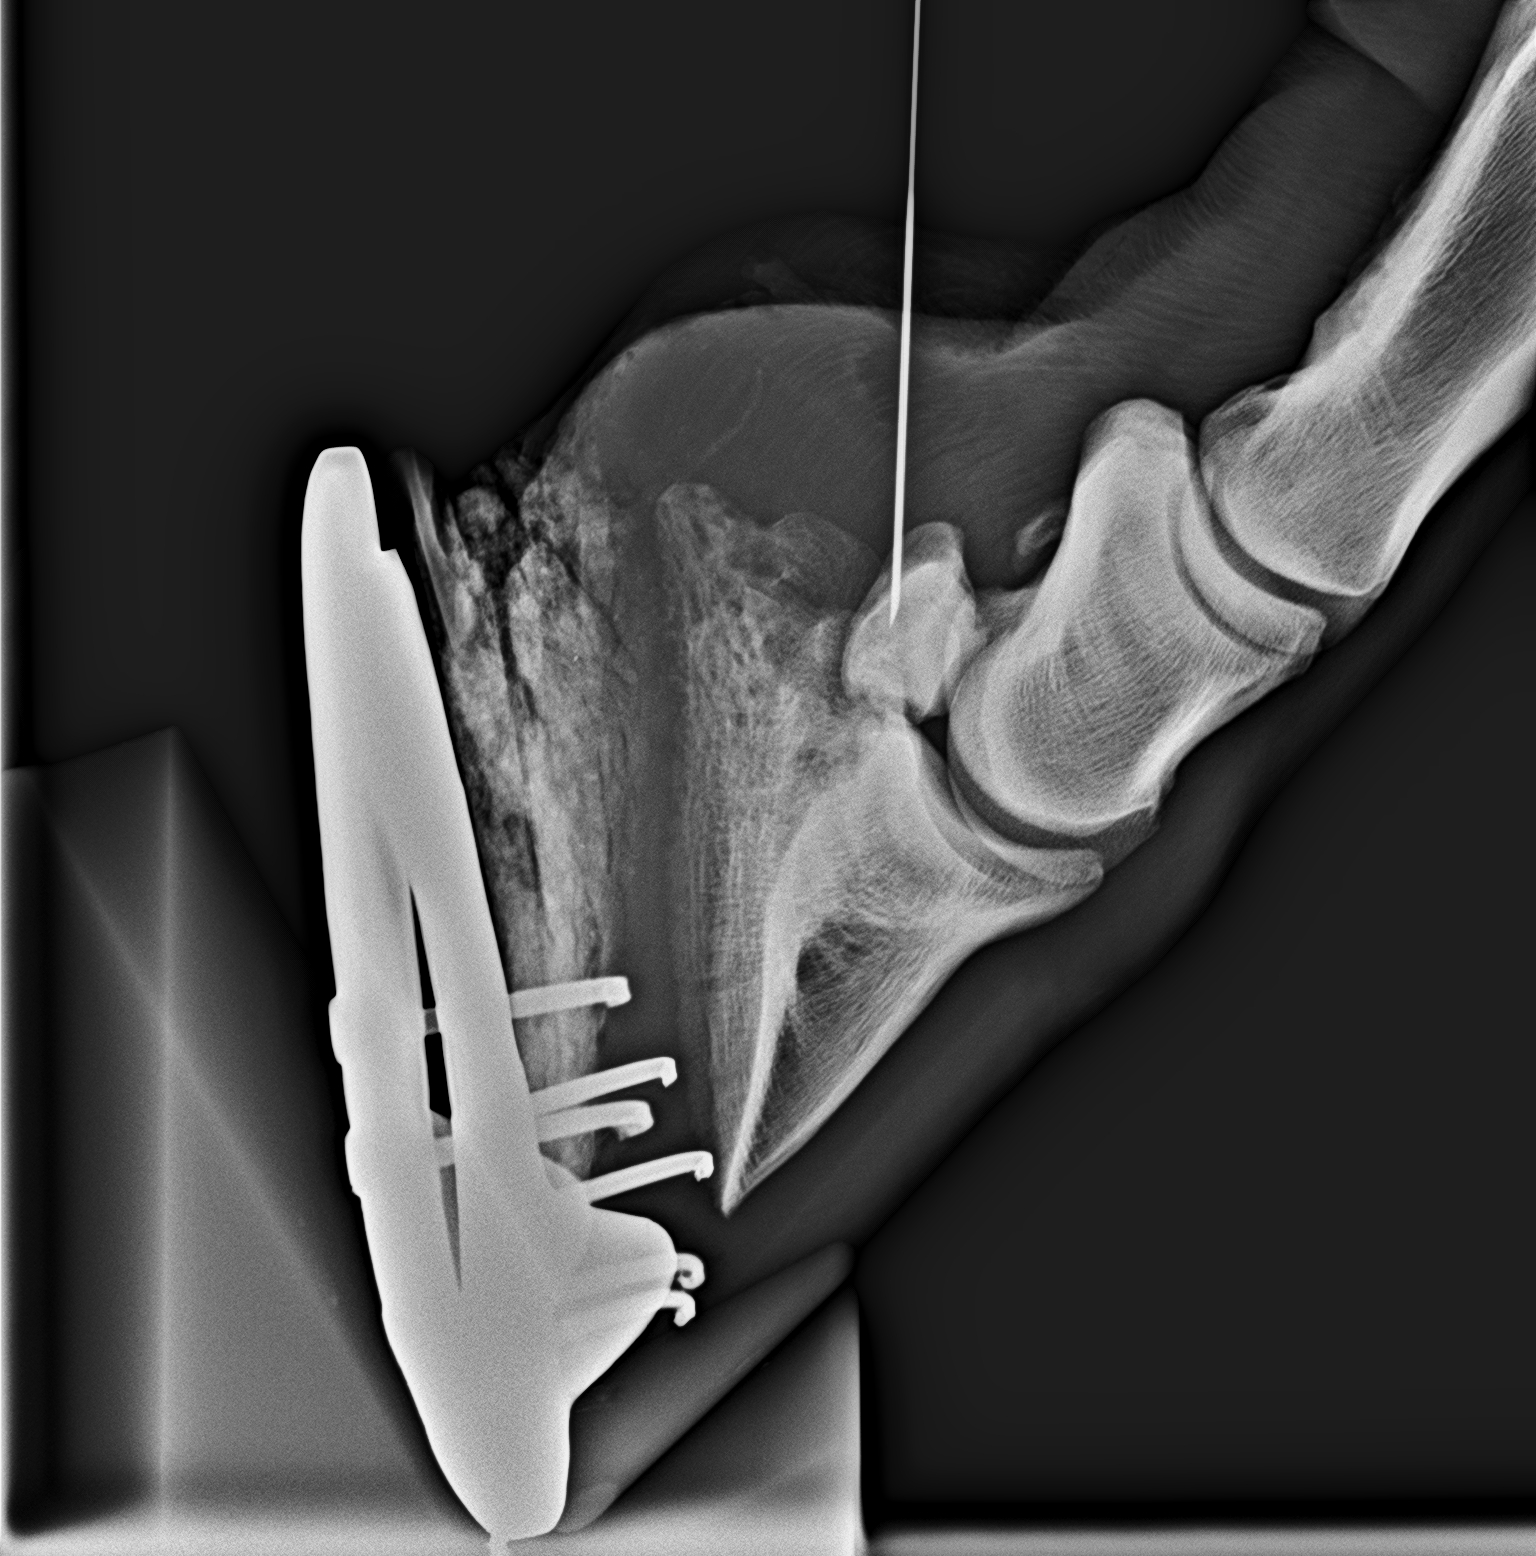

A nyírcsonti burza beinjekciózása.

A szúrás helyességét röntgennel ellenőrizzük.